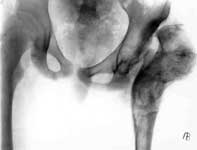

3.Демонтаж аппарата Илизарова.

4.Результат лечения.